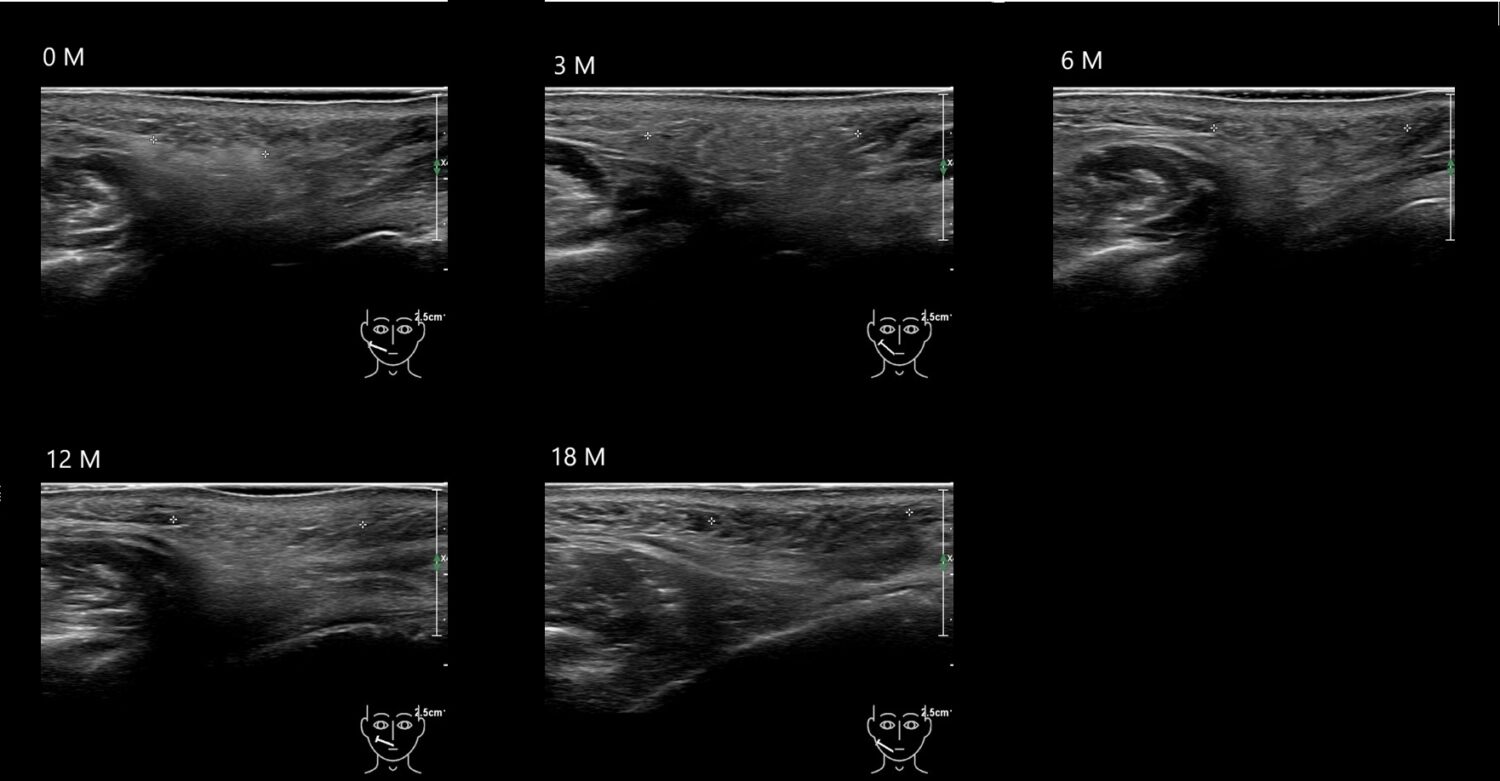

Fillers

Draw in the second image below where the fillers are located. To check if your answer is correct, swipe the first image to the right.